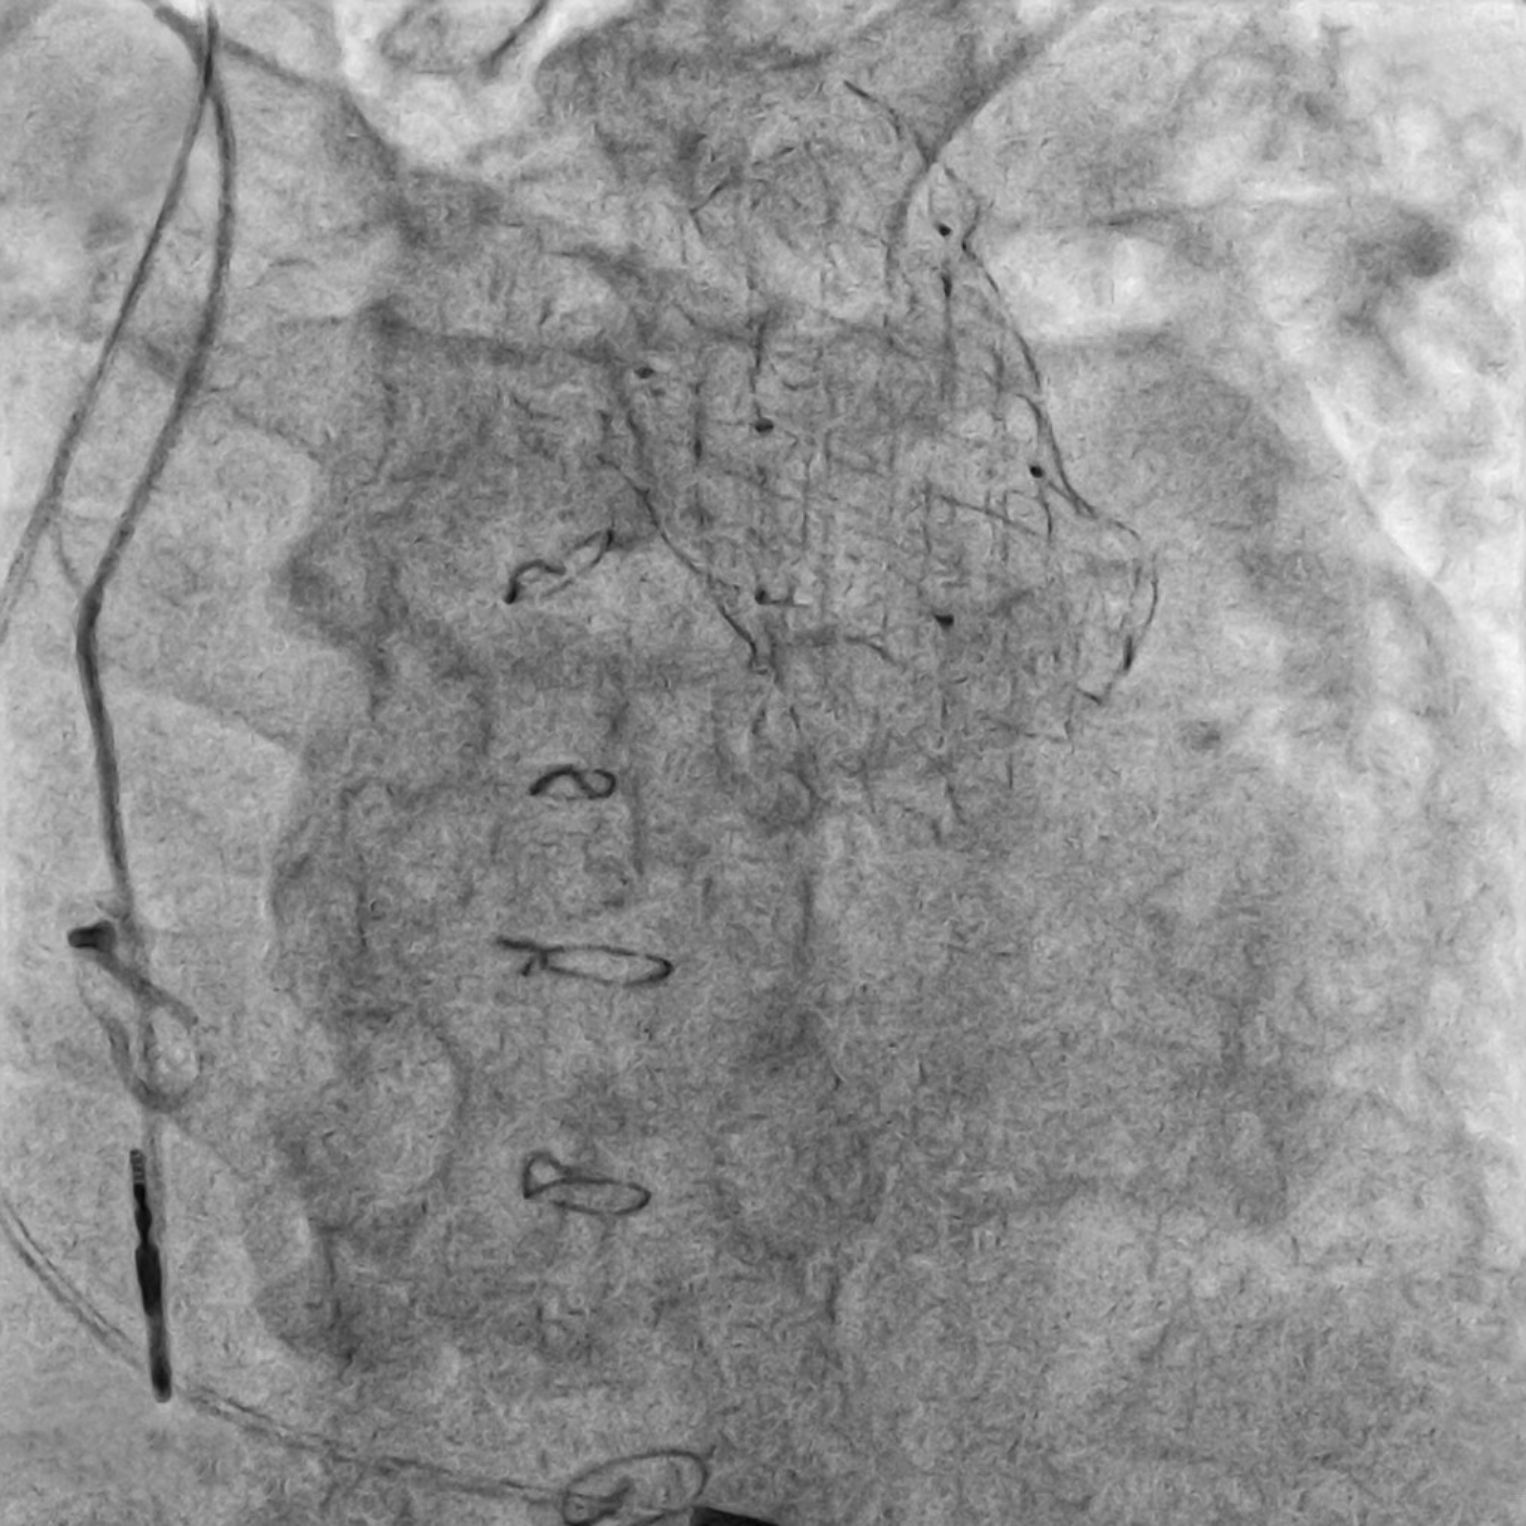

X-ray image with a fine, net-like mesh.

Clinic for Pediatric Cardiology and Congenital Heart Disease

Venus valve – a new solution to an old problem

Adults with congenital heart disease have often undergone numerous operations. At Heidelberg University Hospital (UKHD), a new pulmonary valve prosthesis is now available that can be implanted in previously operated adults – using a minimally invasive technique.

What is the Venus valve?

The Venus valve is a new type of pulmonary valve prosthesis. It can be implanted via catheter, meaning no open-heart surgery is required. This is particularly beneficial for adults whose right ventricle has undergone significant changes in the area of the pulmonary valve. Many existing prosthetic valves have not been suitable for them. Although the number of procedures using the Venus valve will likely remain small, it represents a significant improvement for affected patients.